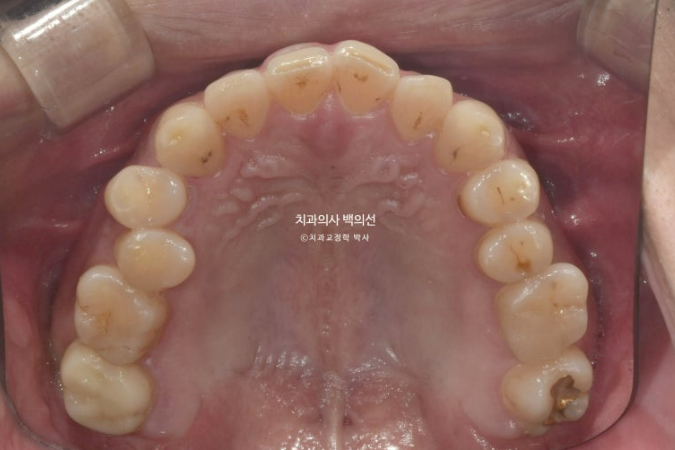

비발치로 아래 전체 치열을 사랑니 공간으로 밀어서 앞니 반대교합을 해소하기로 했습니다.

클리피씨 교정을 선택하셨고 먼저 아래 장치 부착 후 치료를 시작했습니다.

아래 장치 부착 4개월 후 위 장치 부착을 했습니다.

아래에 미니스크류를 심고 사랑니 공간으로 전체치열을 미는 중 입니다.

가려서 보이지 않던 윗니가 드디어 모습을 드러냈습니다.

철사유지장치까지 부착된 모습입니다.